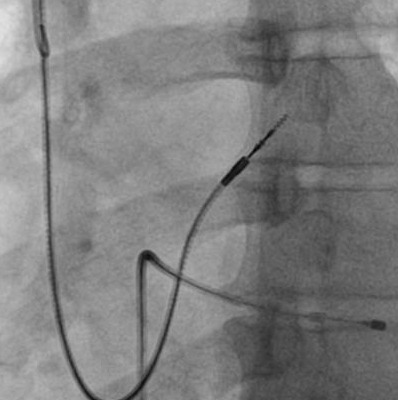

Extra loop

alpha_loop.jpg